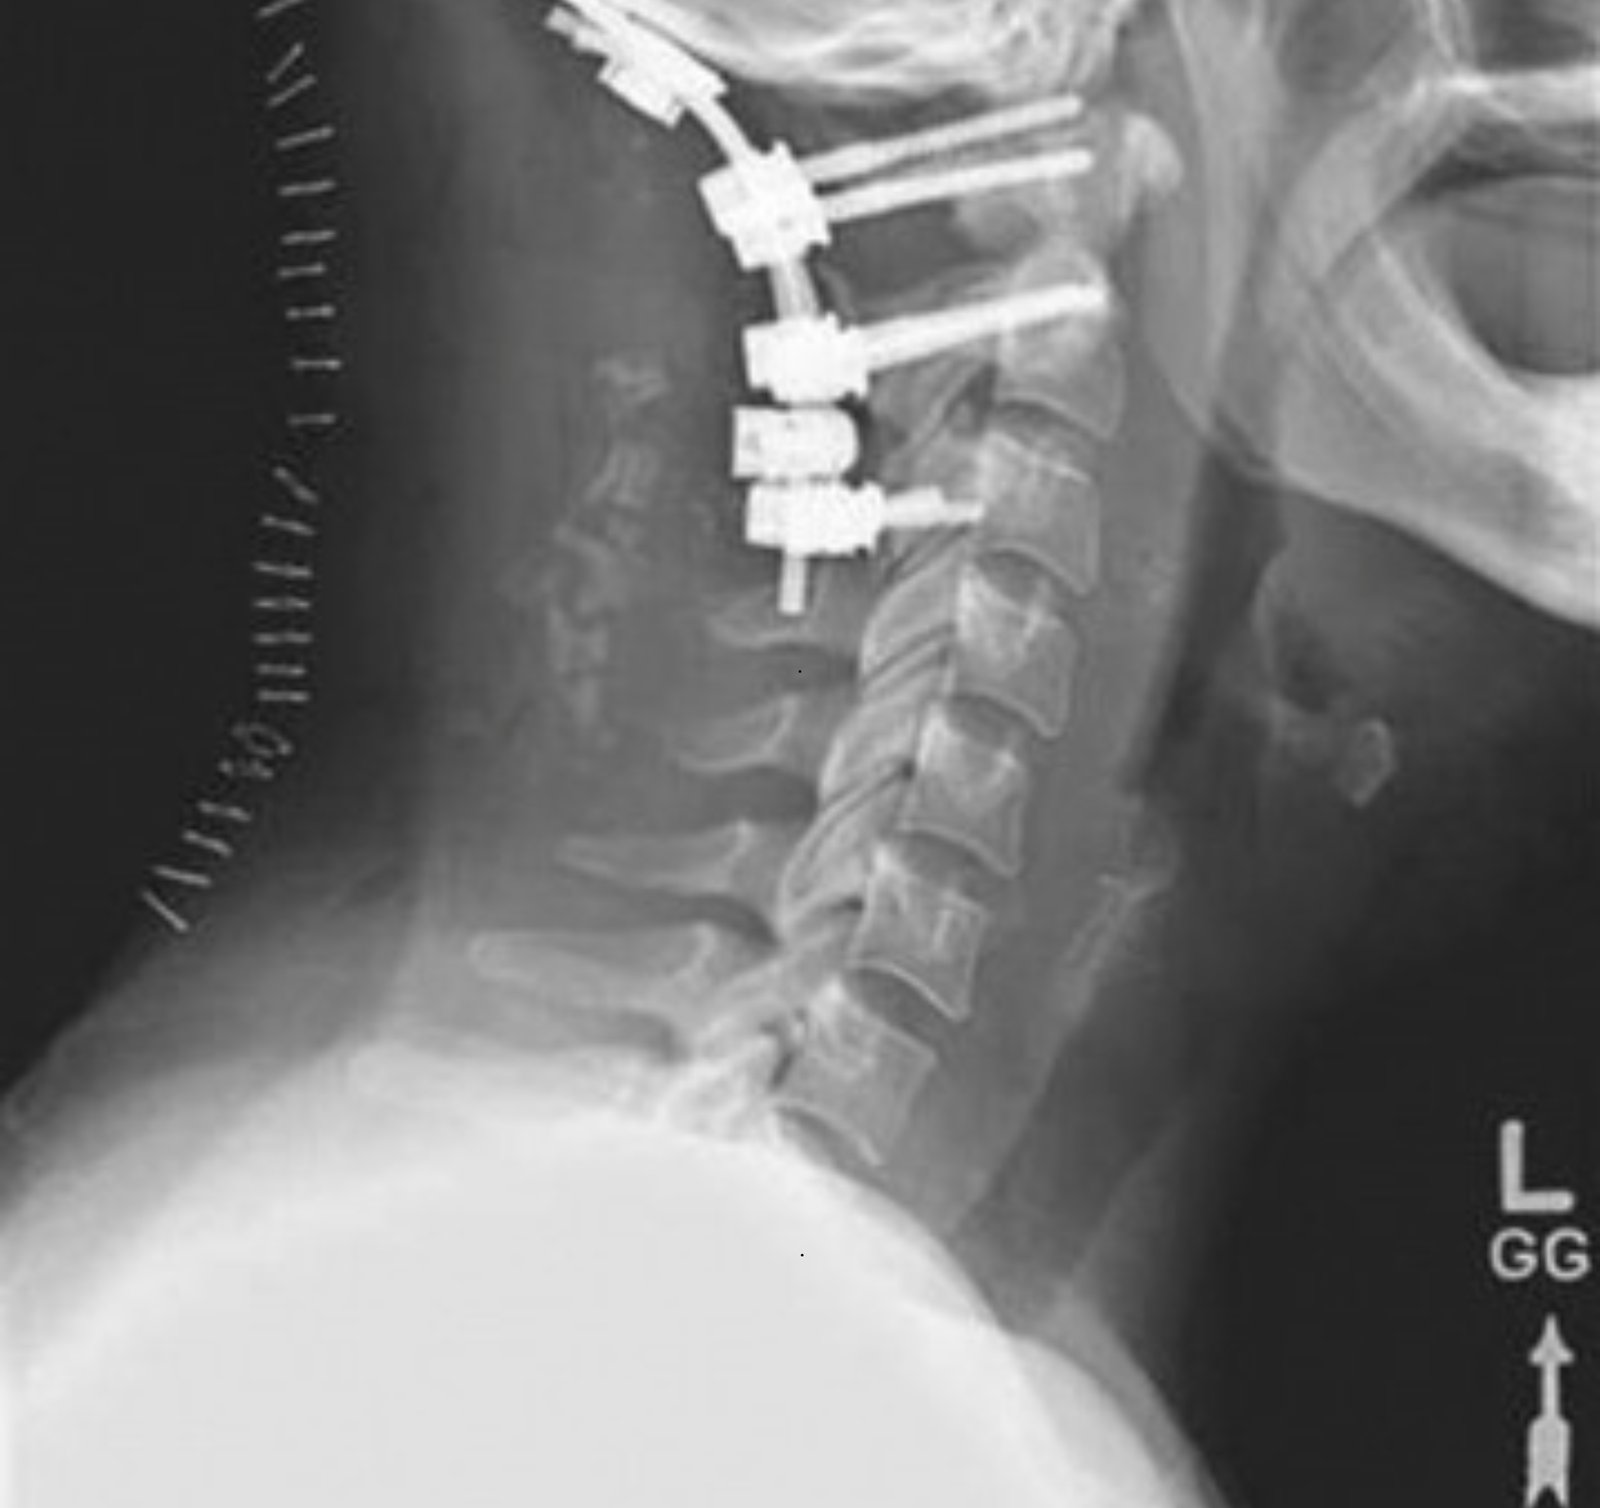

At LeftyNeurosurgeon, we specialize in providing cutting-edge neurosurgical care for brain and spine health. Led by Dr. Deepak Lohia, a recognized leader in Minimal Invasive Neurosurgery and Neuroendovascular Surgery, we are dedicated to transforming lives through advanced treatments and compassionate care.

Our clinic combines state-of-the-art technology with years of expertise to offer precision-based surgeries that ensure faster recovery, reduced risks, and improved outcomes for our patients. We focus on minimizing discomfort and maximizing recovery, utilizing minimally invasive techniques wherever possible.

Minimally invasive neurosurgery involves performing surgeries with small incisions and using advanced technology, resulting in less pain, quicker recovery, and minimal scarring compared to traditional surgery methods. It’s used for brain and spine surgeries, including tumor removal and spinal decompression.